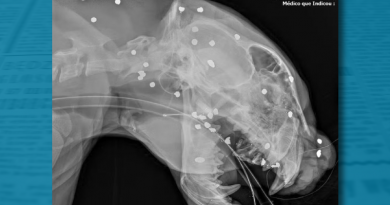

No Brasil, a pena máxima para estupro sem lesão corporal grave e com a vítima viva é de 15 anos de prisão. Isso se aplica, por exemplo, ao caso de um pai recentemente preso por abusar da filha de 17 anos, que ficou na UTI após uma parada cardiorrespiratória com sequelas.

A pena mínima para esse crime é de 8 anos de reclusão. O homem foi detido em 13 de maio e é réu por estupro de vulnerável, mas nega veementemente as acusações.